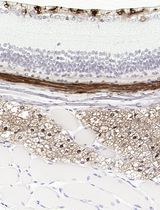

Cover of Cancer Research, featuring study using the protocol.

Cancer Research